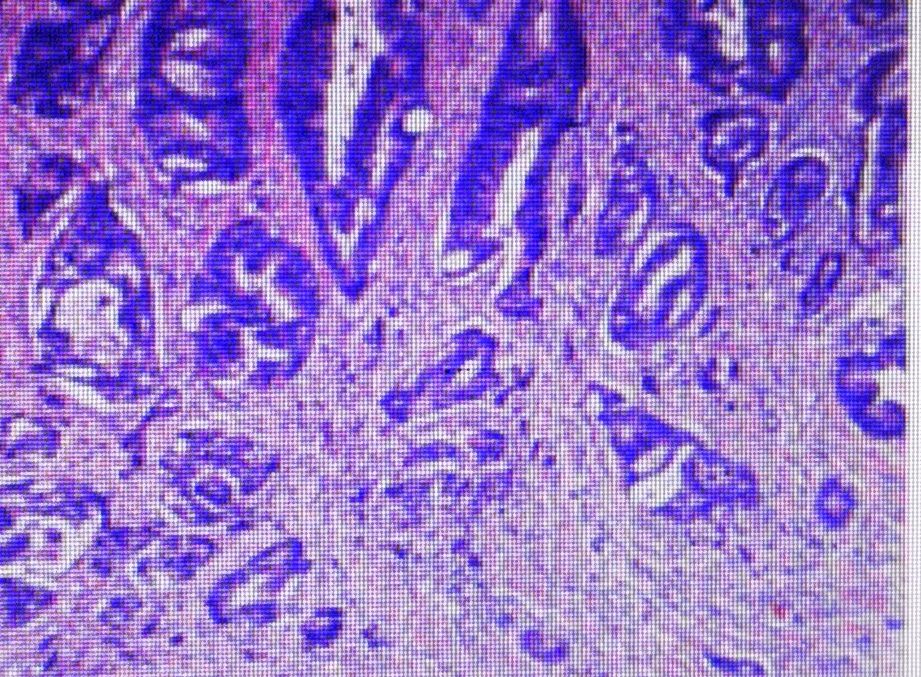

术后病理检查

病理检查图片